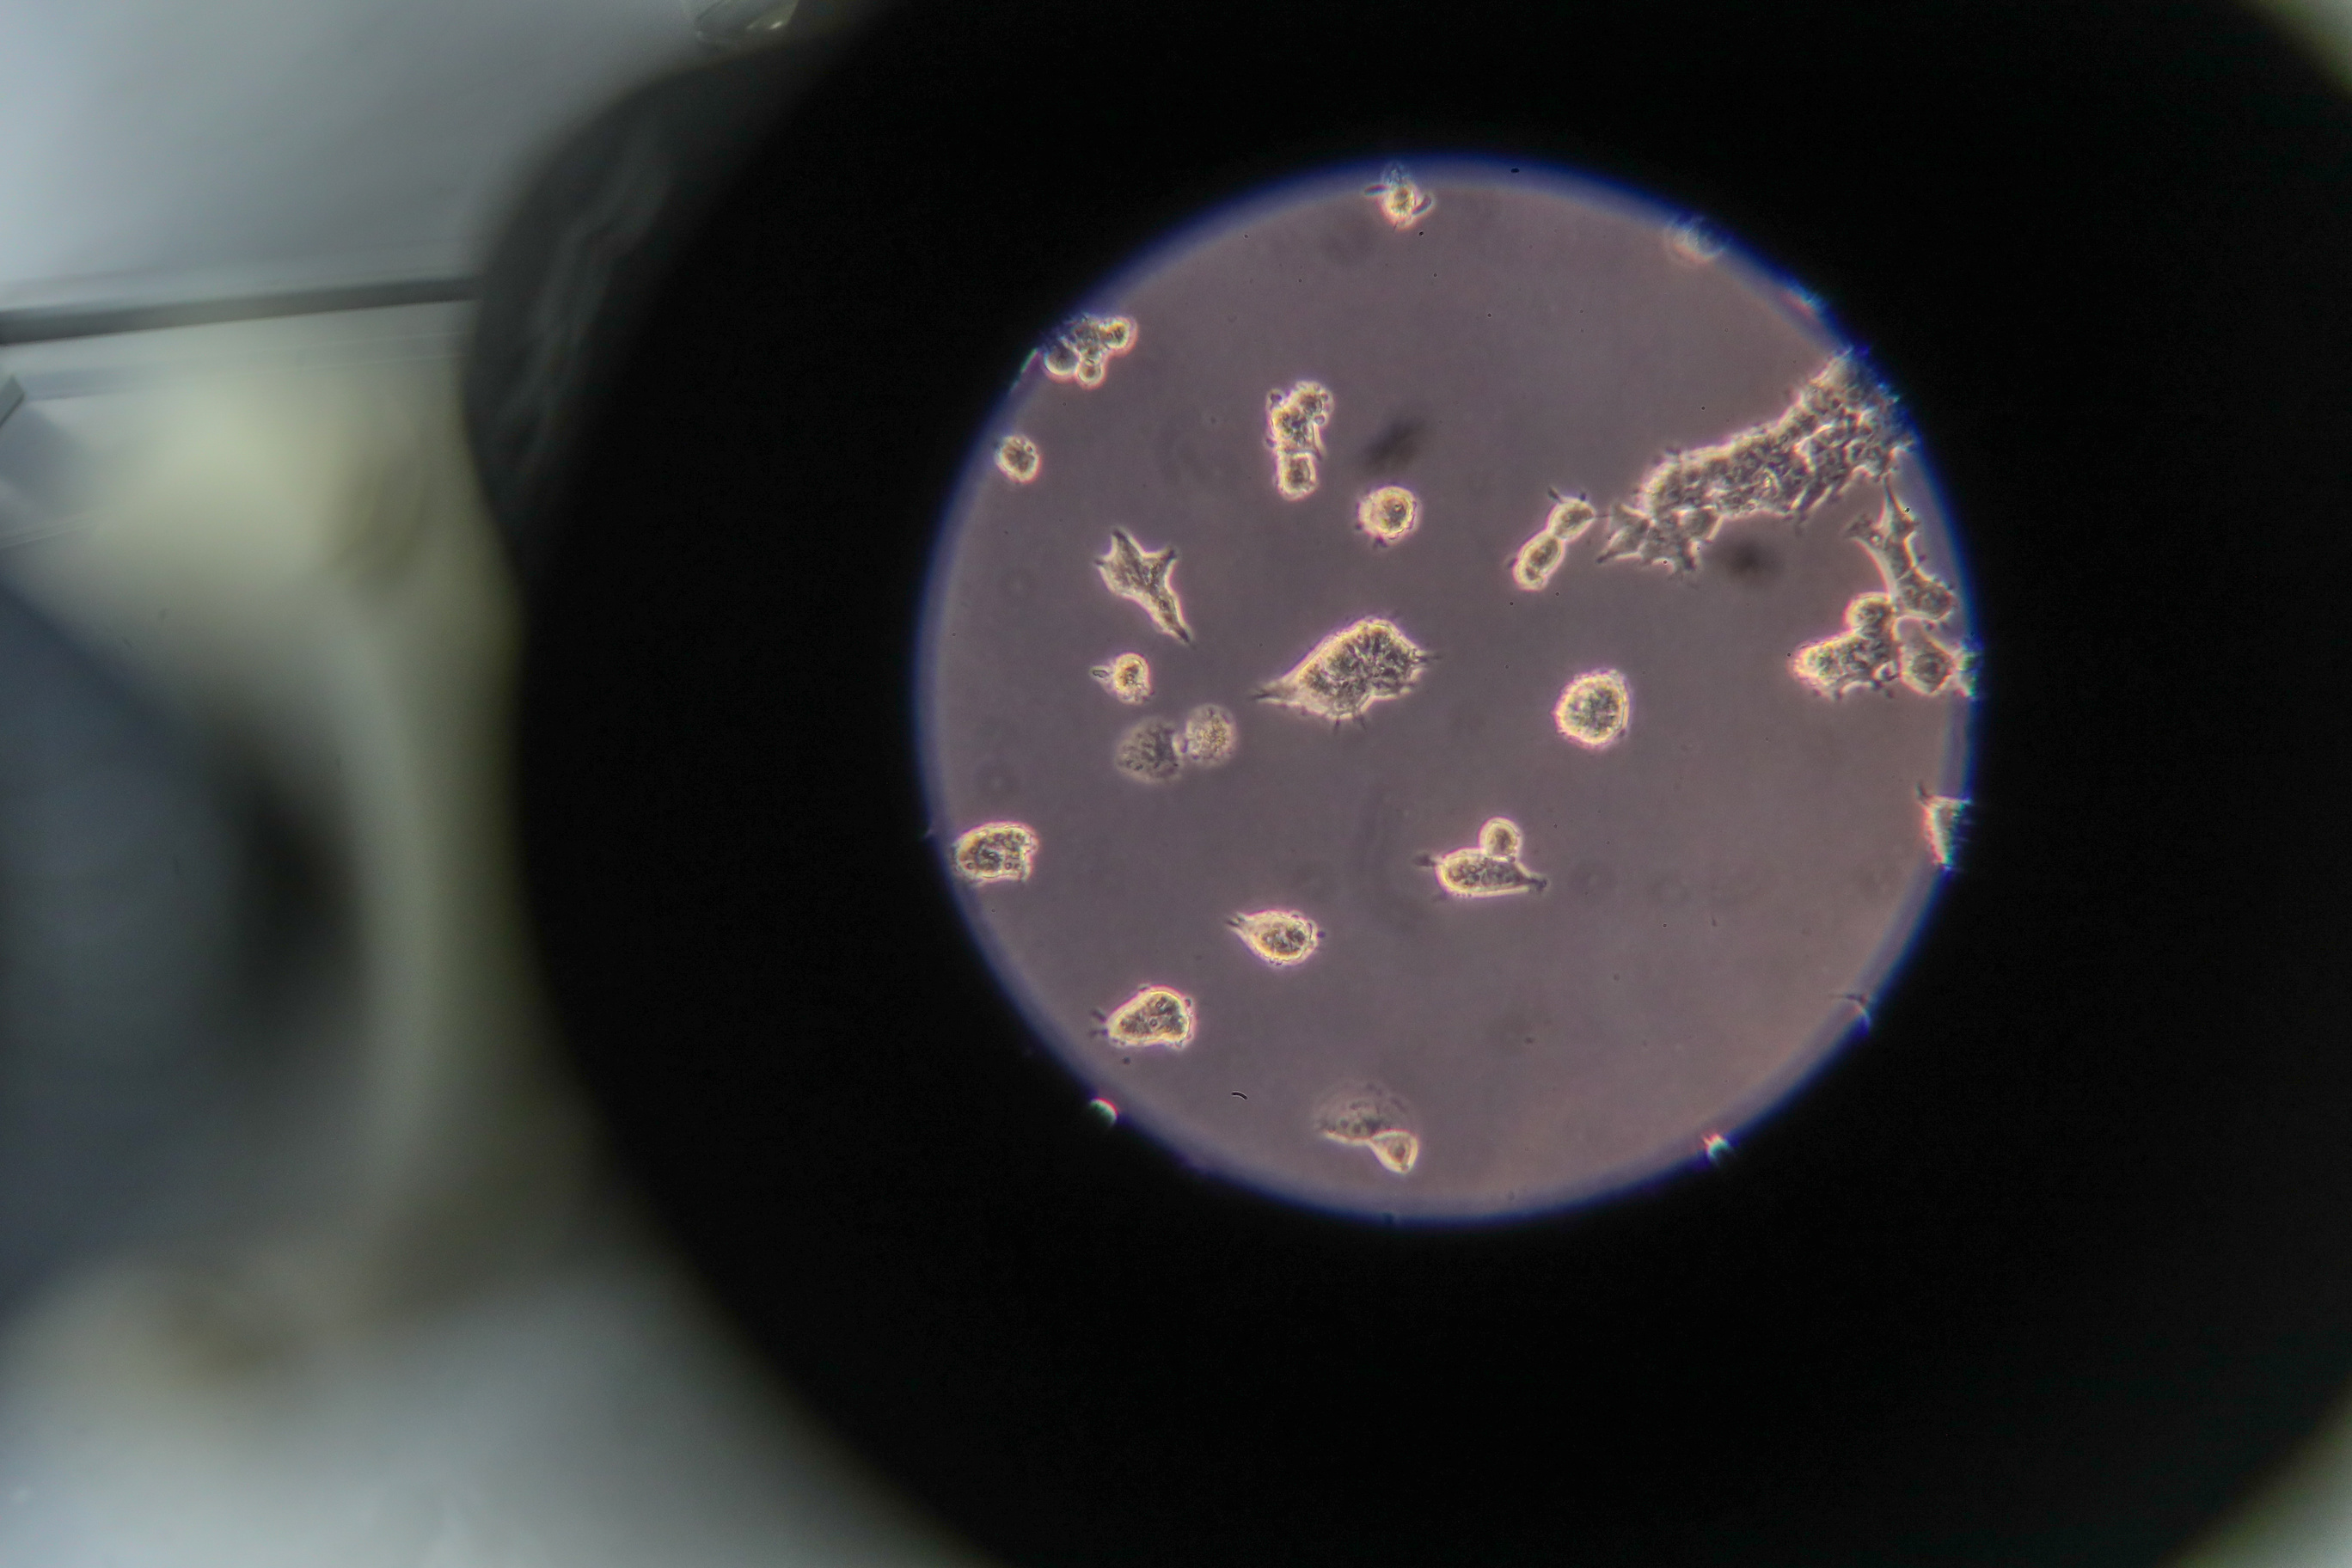

MOSCOW, December 15. /TASS/. Russia’s Federal Medical Biological Agency (FMBA) jointly with the Pirogov Medical University of the Russian Healthcare Ministry has developed a diagnostic technique for determining cellular immunity to the coronavirus, the agency’s press service told TASS. "Russia’s Federal Medical Biological Agency jointly with the Pirogov Medical University of the Russian Healthcare Ministry developed a unique diagnostic technique to determine a repertoire of T-cell receptors specific to SARS-CoV-2 based on a targeted sequencing of the next-generation human DNA. An analysis of the SARS-CoV-2-specific T-cell clonotypes in the experimental sampling demonstrated a high correlation between the presence of humoral and cellular immunity - the absolute majority of seropositive individuals have a SARS-CoV-2-specific T-cellular response," the press service said. At the same time, 30% of individuals who had the coronavirus infection and don’t have antibodies, have T-cells. Those who did not have COVID-19 and don’t possess the humoral immunity to the infection, in some cases have the T-cell clonotypes. This, according to the FMBA, allows to presume the presence of a pre-existing T-cellular immunity conditioned by seasonal coronaviruses or other agents of acute respiratory viral infections. "This observation requires further research. The developed technique removes a number of limitations (complexity of the analysis, the necessity to rush the delivery of a biological material to the laboratory, and so on) which are characteristic of traditional low-output methods of the T-cellular immunity analysis and presents an opportunity to incorporate this method in population studies," the press service noted. It is possible to fully evaluate the state of the humoral and cellular immunity to the coronavirus in population only after conducting special tests planned for 2021. Read more